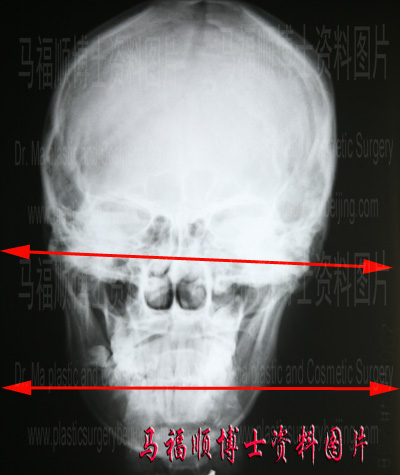

判断有没有颌面骨骼中线扭曲的简单方法就是X线测量法。其原理是选择上面部的一个平面作为参考,检查牙齿的咬合面是否与这一参考平面平行。平行时认为面部的中线没有扭曲,不平行且夹角超过一定角度时则认为有中线扭曲。这位受术者术前X线片中(见右侧图片),下面一条红线所代表的是牙齿的咬合平面。上面红线是经过两眶骨下缘的连线,可做为上面部平面的参考线。如果面部中线不扭曲的话,这两条线是完全平行的。如果这两条线不平行而且其夹角大于15度,则说明中颌面骨的中线有明显的扭曲、或者说有明显的弯曲。

牙齿的咬合平面与眶下缘的连线不平行,但夹角小于15度,说明颌面部中线扭曲不明显。

术前对本例受术者的X线中线评估显示,其咬合面与上面部参考线不平行,但所形成的夹角小于15度。所以手术设计时就没有建议进行面部中心线矫正。结果术后仍然能有满意的效果。所以对于面部不对称整形来说,最重要的是术前能够认真地分析每位受术者面部的具体情况,并做出相应的手术设计,原则上以用最简单的手术,最大程度地恢复对称性为佳。对于哪些有明显中线扭曲的受术者,则不应该首先选择姑息性手术或是掩饰性美容手术,应该首先调整中线的畸形,并在此基础上分期进行其它一些手术。只有这样才能取得最佳的美容效果,同时也能在最大程度上恢复可能存在的功能障碍。